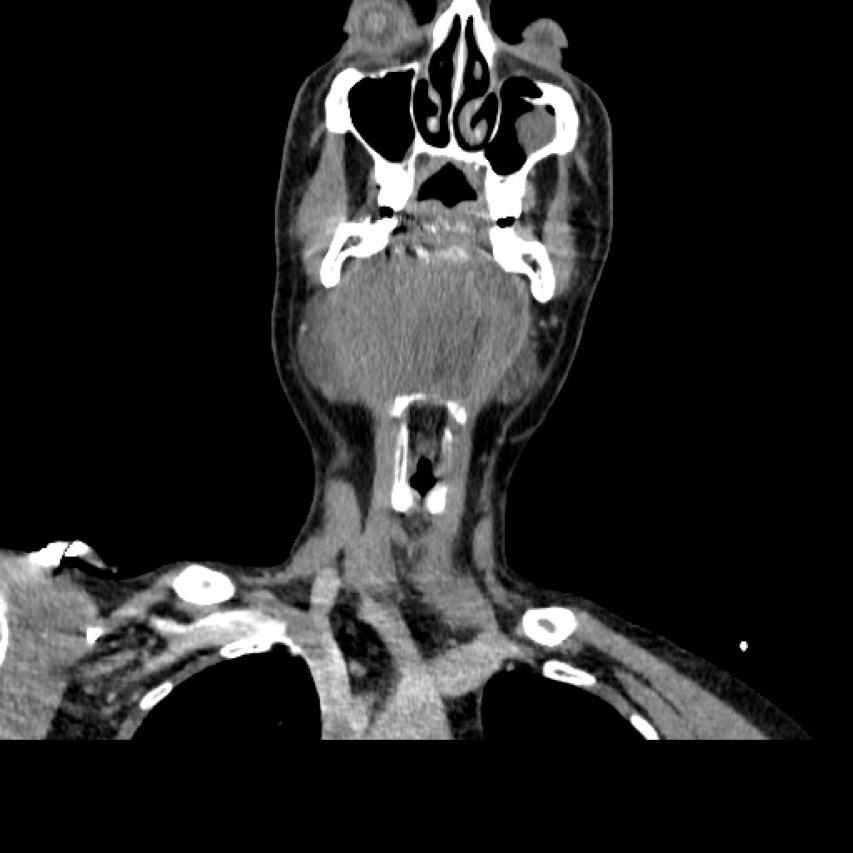

Initial investigations included blood tests and an orthopantomogram (OPG). The INR was 26. The OPG showed a large periapical radiolucency associated with the lower left lateral incisor which had previous endodontic treatment but no dental / bony cause for his advanced neck swelling was identified. A CT scan (Figure 1, 2 and 3) indicated that there were soft tissue density masses present within the floor of the mouth. They most likely represented a haematoma but an abscess could not be excluded. The airway was markedly compromised. He was immediately planned for surgical intervention with the input of the haematologist and anaesthetist, along with urgent treatment to reverse the effects of Warfarin.

Figure 1 (coronal view).

Figure 3 (transverse view): CT showing a large indistinct mass / swelling of the submandibular and submental spaces with compression and deviation of the airway. Not a typical appearance of an abscess.